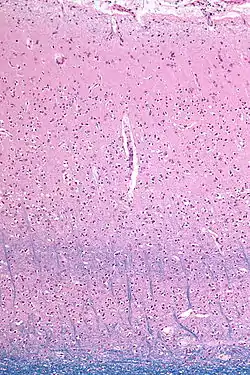

Micrograph showing the visual cortex (predominantly pink). The blue, horizontal band in the lower half of the image are the bands of Baillarger/the line of Gennari. Subcortical white matter (predominantly blue) is seen at the very bottom of the image. HE-LFB stain. | |